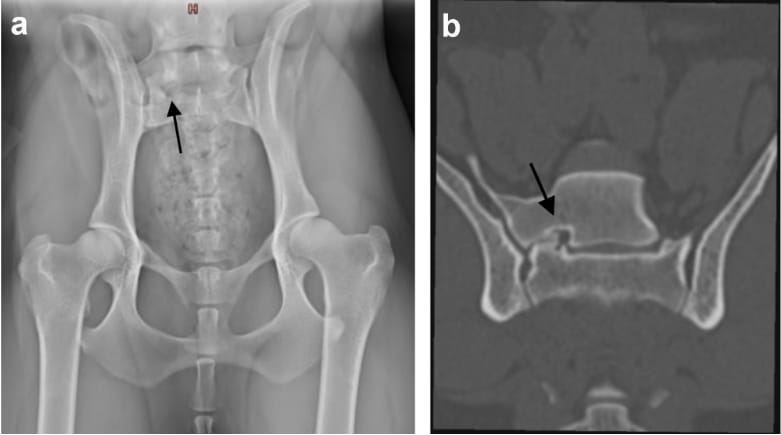

(a+b) a) A ventrodorsal radiograph, b) Computed tomography (CT) dorsal bone window. A female Brittany, 3.3 years old, illustrating a lumbosacral transitional vertebra (LTV) type 3 [8] with an articulation of the LTV segment with sacrum on the right side, causing ipsilateral foraminal stenosis of the sacral foramen (black arrow)